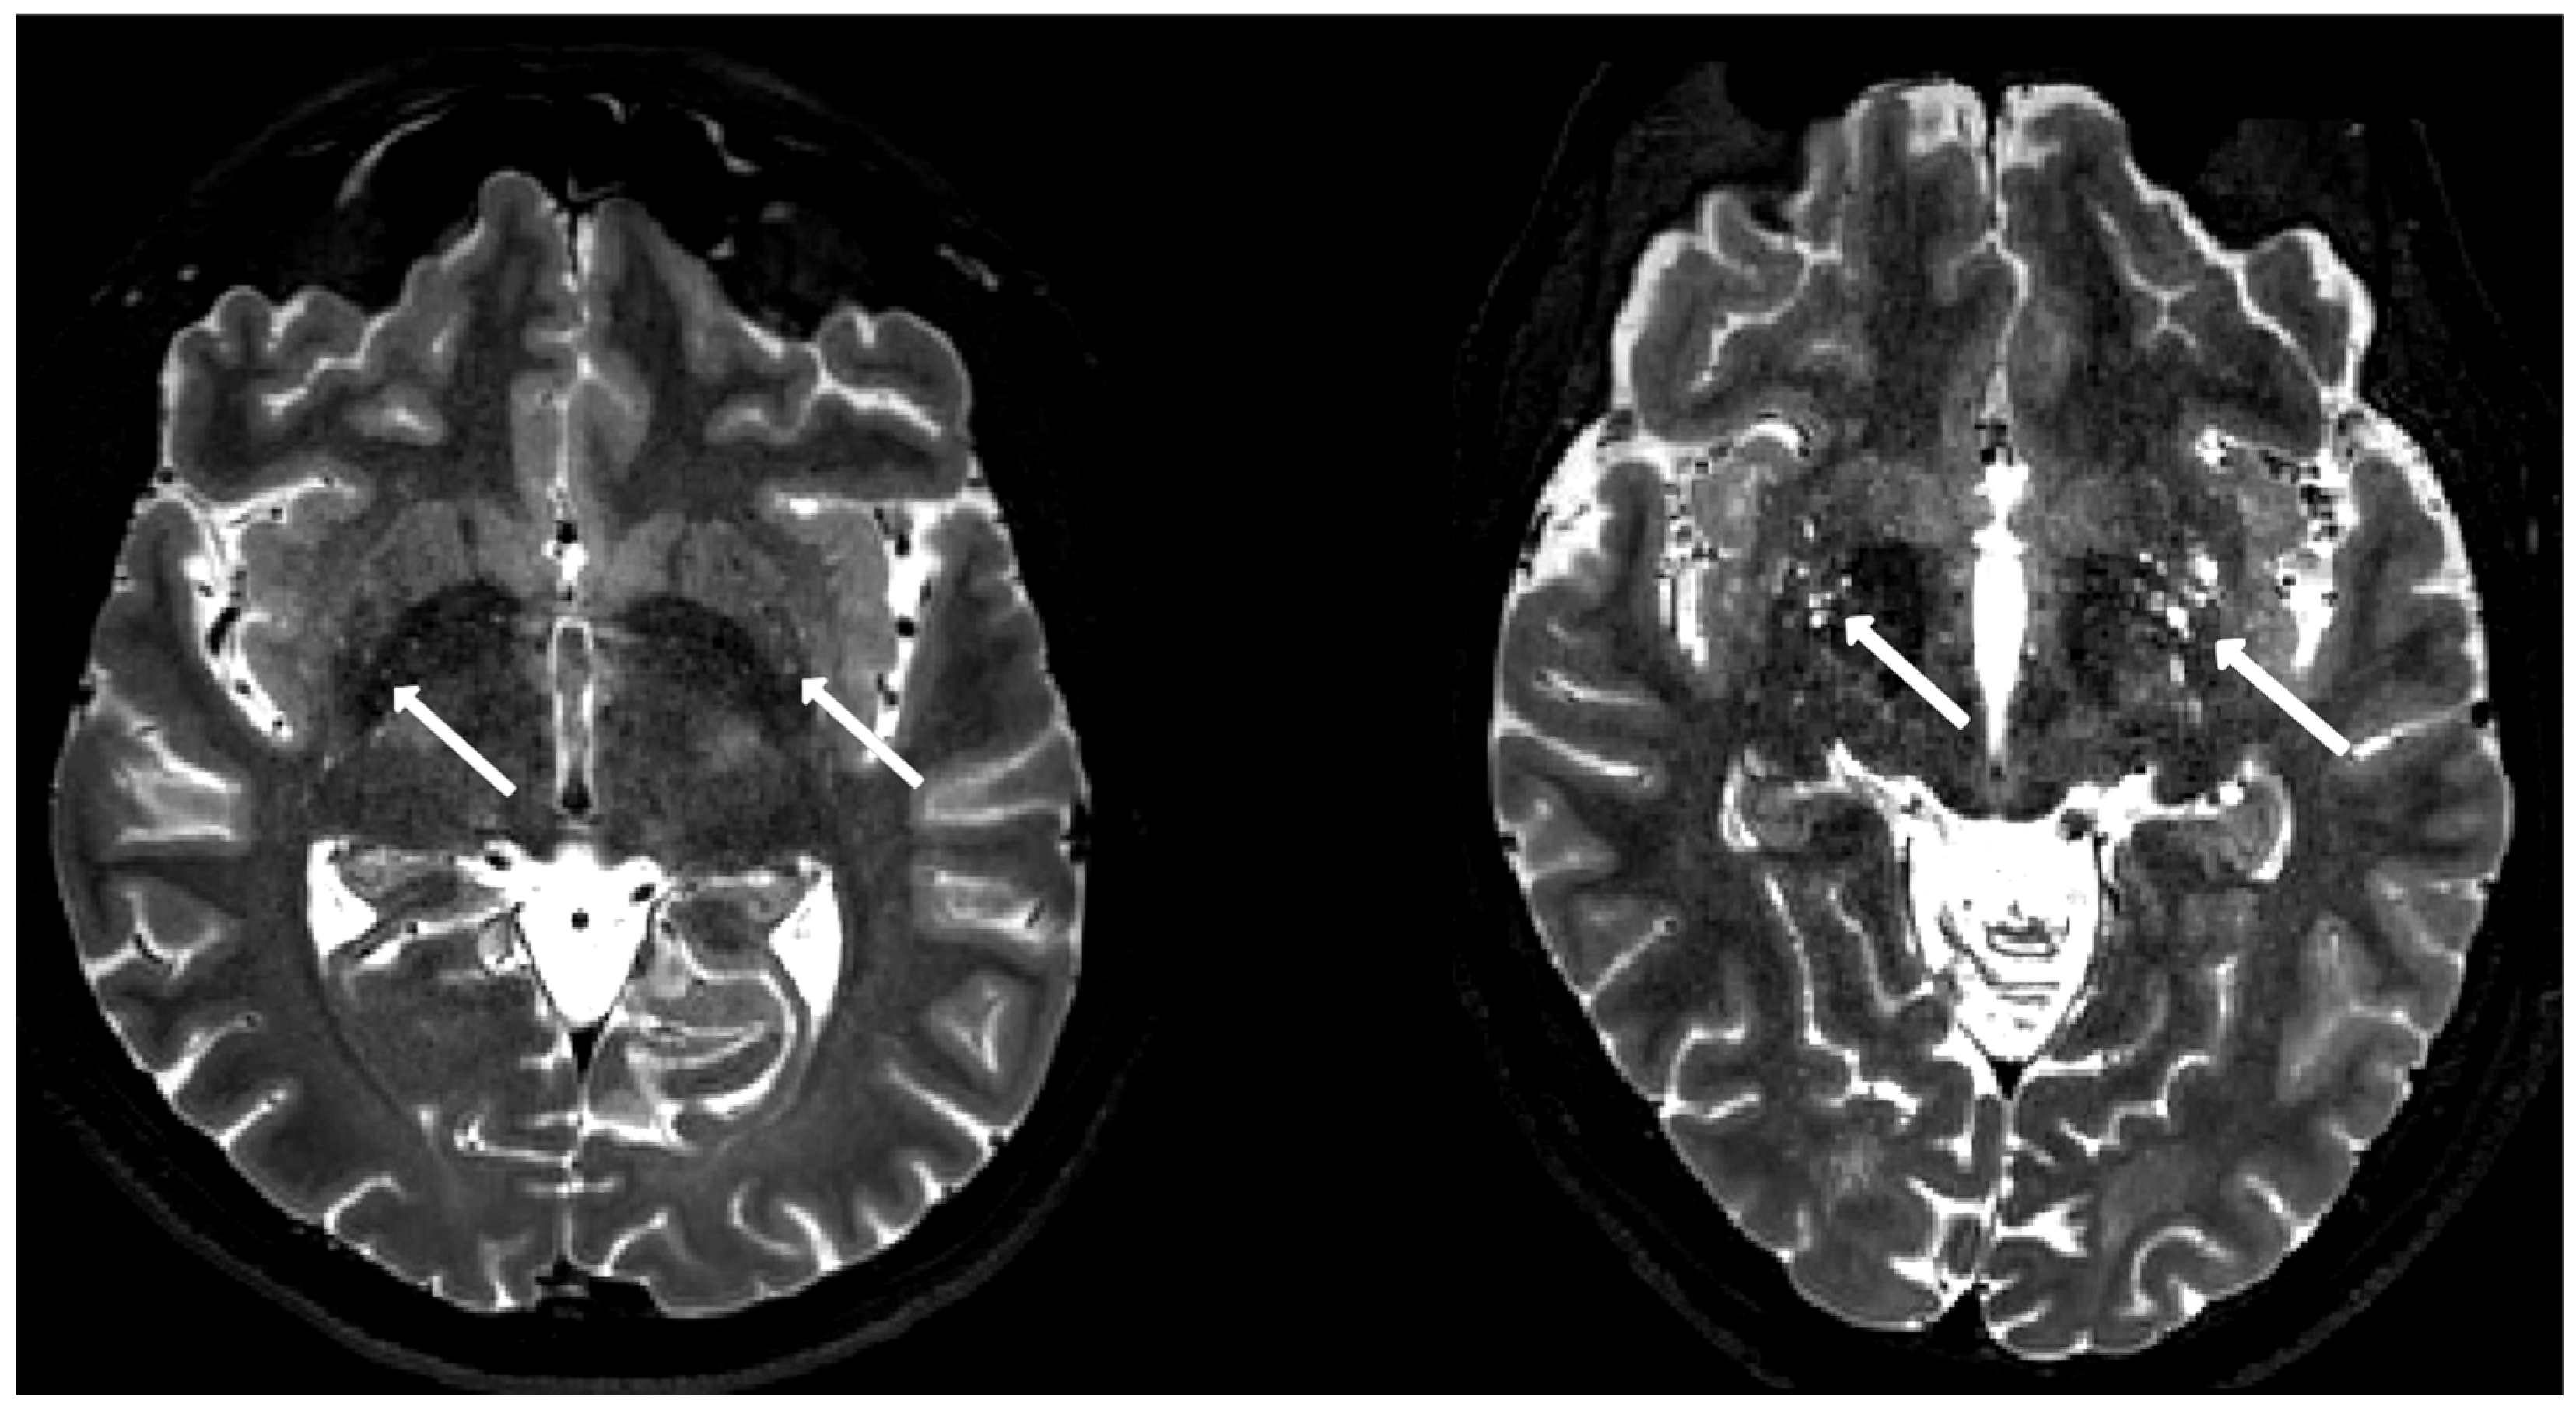

Two exemplary axial T2-weighted images at the basal ganglia level are shown in Figure 3 to demonstrate the spectrum of EPVS appearance. The result of the visual EPVS rating is summarized in Figure 4.

Figure 3. Examples of mild EPVS from a control subject (left) and high EPVS from a patient subject (right) are presented on a T2-weighted image. EPVS in the basal ganglia are indicated by arrows.